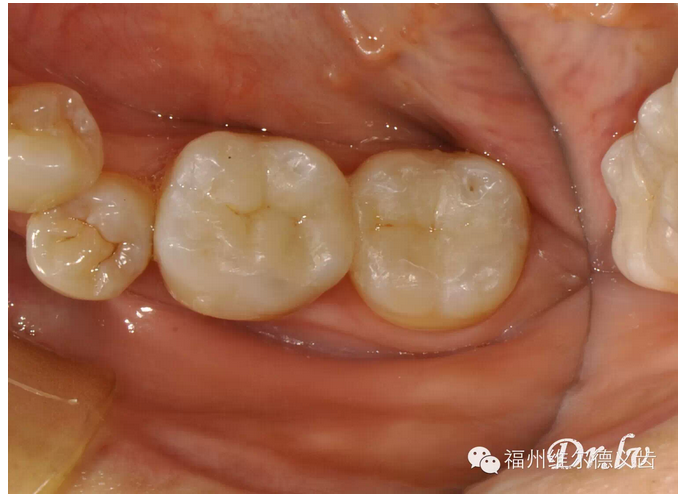

這次機會又沒抓住的話,牙的齲壞開始深了,涉及的牙面多了,這時候單純補牙不行了,需要做嵌體,才能把壞的部分修補好,嵌體要幾百到兩三千不等,有點貴了。

QQ圖片20150725100145.png

QQ圖片20150725100158.png